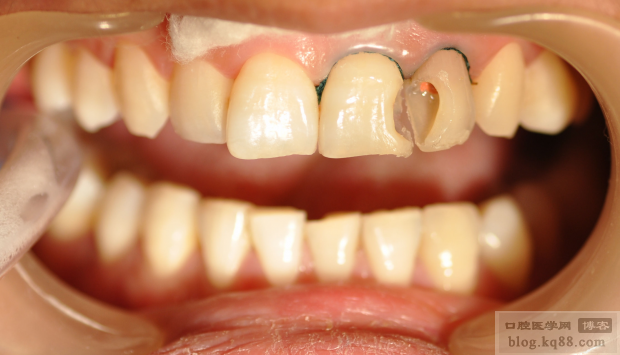

患者,女,28歲,前牙原充填材料脫落來診。

檢查:21遠中22近中充填物脫落,色暗,21牙冠變色

治療方案:1:21樹脂美容性修復(fù)

2:22一次性根管充填,建議冠套修復(fù)(患者考慮經(jīng)濟因素,強烈要求先充填)

22根尖區(qū)陰影,但是該牙未見明顯不適,所以行一次性根管治療(插針片和根充片如下)